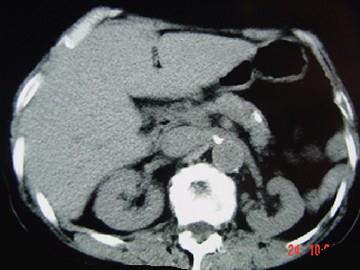

问题 女,54岁,中上腹痛,体重减轻,消化不良,脂肪痢、便量多、泡沫状。影像检查如下图,最佳诊断是 ( )

选项 A.急性胰腺炎 B.慢性胰腺炎 C.胰腺癌 D.急性出血坏死性胰腺炎 E.胰岛素瘤

答案 B